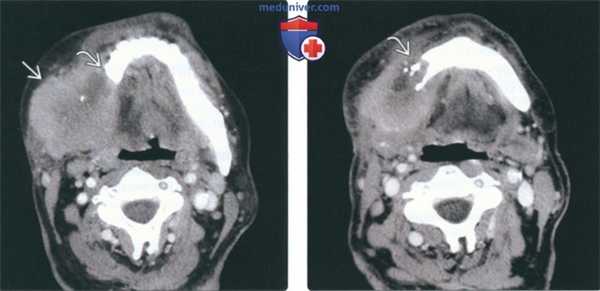

(Слева) МРТ Т1ВИ в аксиальной проекции. Саркома Юинга, локализующаяся в жевательном пространстве. Обратите внимание, что сигнал относительно здоровых мышц гиперинтенсивный. Нижняя челюсть разрушена, определяется лишь небольшой ее фрагмент. Жировая клетчатка окологлоточного пространства смещена в медиальную сторону.

(Справа) МРТ Т2ВИ FS, аксиальная проекция, тот же пациент. Неоднородный сигнал высокой интенсивности. Крупный лимфоузел в заглоточном пространстве слева представляет собой случайную находку.

(Слева) На аксиальной МРТ (Т1ВИ) в жевательном пространстве визуализируется саркома Юинга в виде огромного объемного образования с гиперинтенсивным относительно мышц сигналом. Ветвь нижней челюсти разрушена, на этом изображении виден лишь ее мелкий фрагмент. Полоска окологлоточного жира смещена кнутри.

(Справа) На аксиальной МРТ (Т2ВИ FS) у этого же пациента определяется неоднородный сигнал крайне высокой интенсивности в опухоли. Хорошо различимый заглоточный лимфоузел слева является случайной находкой.